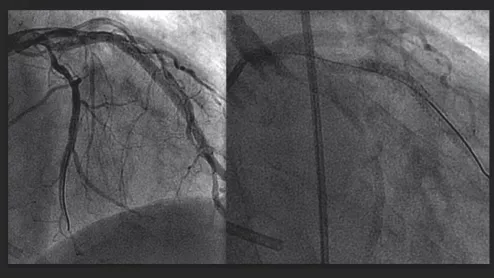

A comparison between a traditional iodine contrast angiogram (left), and a gadolinium contrast angiogram (right). MRI gadolinium contrast is starting to be used in some interventional radiology procedures and is being considered in interventional cardiology due to the iodine contrast shortage.

Gadolinium might be an alternative, stop-gap solution for interventional procedures during the current iodine contrast shortage.

The imaging iodine contrast shortage is delaying procedures and causing rationing at hospitals. impact is it having on hospitals and the tough decisions that are being made to triage patients to determine if they will get a contrast CT scan or an interventional or surgical procedure requiring contrast. Photo by Dave Fornell